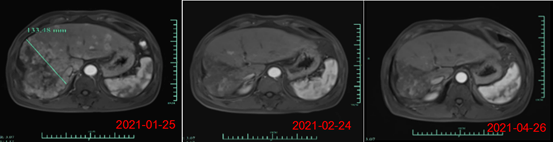

As of March 10, 2021, a total of 11 patients were enrolled into this study. All subjects had advanced HCC and had failed prior lines of treatment including chemotherapy, TACE, and targeted therapies. All subjects had BCLC stage C (late stage) HCC except for one subject with stage B (mid stage). All subjects had multiple lesions, of which 6 (54%) had distant metastasis. Two subjects dropped out early and were not evaluable. Among the 9 evaluable subjects, 4 achieved partial response (PR), 3 achieved stable disease (SD), and 2 had disease progression (PD). The objective response rate was 44.4%, and the disease control rate reached 77.8%. A partial response lasting for more than 6 months was observed in Subject 007 at the time of data cutoff, whose tumor volume was reduced by more than 80% one month post cell therapy infusion. (As of June 2021, this subject had exceeded 8 months of disease control, follow-up is still ongoing). Good tumor response was also seen in Subject 012, who has advanced and diffuse massive HCC and joined the study after failing in radiotherapy, targeted drug and 12 times of TACE.

On day 28 post infusion with CAR-T cells, the target tumor lesion decreased from 133mm in diameter at baseline to 9mm, a reduction of more than 93%. Currently, the subject is being evaluated for month 3 post CAR-T cell infusion, MRI scan showed near complete tumor response. In addition, AFP level (alpha-fetoprotein, a specific tumor marker for primary liver cancer) decreased from a baseline value of >80,000/ng/ml to 1148.9 ng/ml on month 1, and to 746.7 ng/ml at month 3 post infusion (normal range <40ng/ml), demonstrating significant preliminary efficacy of Ori-CAR-001 in patients with advanced HCC.